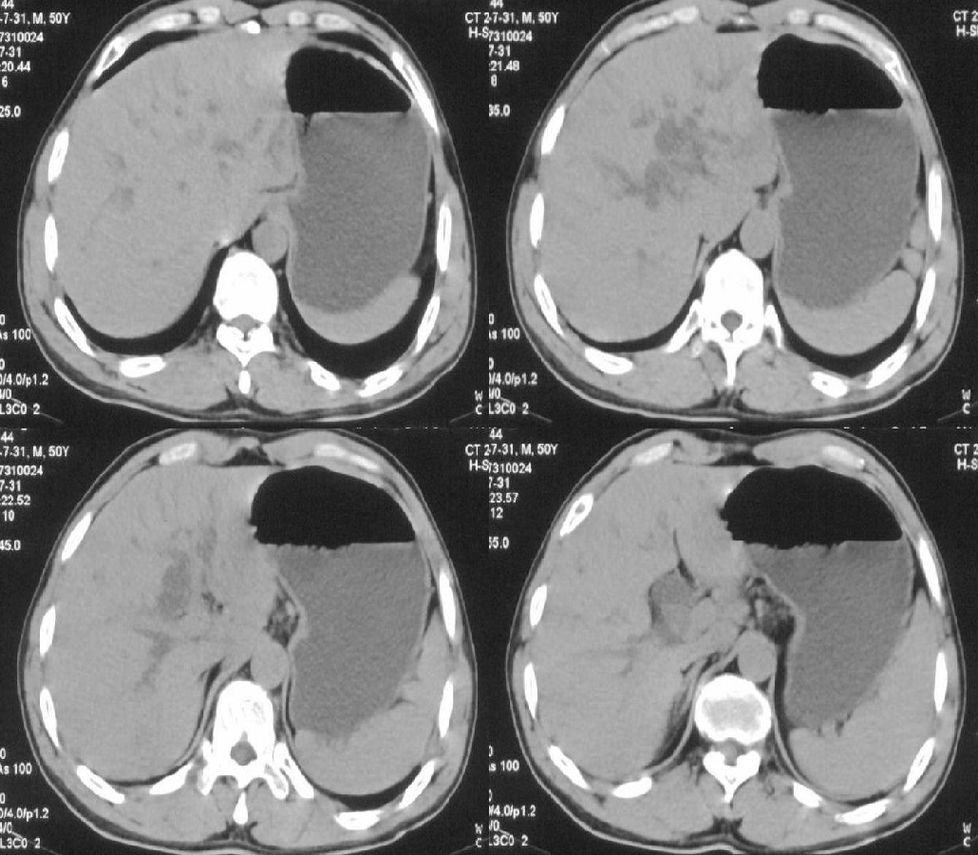

标题: CT21384:男性,50岁。发现无痛性黄疸十余天,B朝提示肝胆管 [打印本页]

标题: CT21384:男性,50岁。发现无痛性黄疸十余天,B朝提示肝胆管

1.考虑:壶腹占位病变(癌?)。

2.胆系低位梗阻:肝内外胆管扩张,胆囊增大,胰管扩张。

胰头癌伴低位胆道梗阻。

胆系低位梗阻(肝内外胆管扩张,胆囊增大,胰管扩张);考虑胰头癌或壶腹癌所致。

胰头强化欠均匀,胆胰管扩张。考虑胰头癌可能性大。

胆系低位梗阻(肝内外胆管扩张,胆囊增大,胰管扩张,钩突似有占位);考虑胰头癌